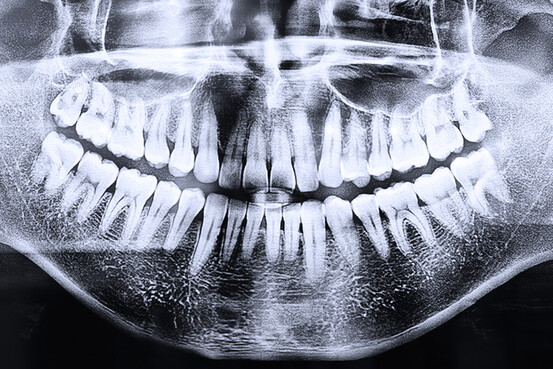

Plaque dentaire : panorama des risques

Le développement de la plaque dentaire expose le sujet à une longue liste de complications. Voici un point sur l'état de nos connaissances en la matière.

Selon leur emplacement sur la plaque dentaire, les bactéries tirent l’énergie dont elles ont besoin de différentes manières. Celles qui vivent en surface puisent directement dans les sucres alimentaires à leur portée, tandis que celles qui vivent dans l’espace gingivodentaire dégradent ces glucides en différents acides organiques (acétique, formique, lactique, etc.) qui ont le pouvoir de dissoudre des cristaux (d’hydroxyapatite plus exactement) contenus dans les dents et les structures osseuses, et ainsi d’y créer caries et autres poches parodontales.